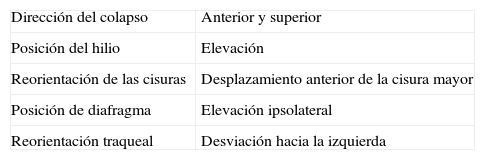

La atelectasia pulmonar es un indicador importante de una enfermedad subyacente, potencialmente grave, que es imprescindible diagnosticar precozmente. Uno de los mecanismos más frecuentes es la reabsorción de aire distal a la obstrucción de las vías respiratorias. La radiografía de tórax es una herramienta excelente para diagnosticarla, especialmente útil para descartar obstrucciones bronquiales centrales (por ejemplo, una neoplasia endobronquial). Si no se reconocen correctamente los signos de la pérdida de volumen el diagnóstico y el tratamiento pueden retrasarse. En este artículo se describen los principales hallazgos radiográficos de la atelectasia pulmonar lobular y su correlación con la tomografía computarizada. Se incluyen los signos clásicos descritos en la bibliografía y otros menos conocidos y a su vez sutiles.

Atelectasis is an important indicator of potentially severe underlying disease that must be diagnosed as early as possible. One of the most common mechanisms is the reabsorption of air distal to respiratory tract obstruction. The chest X-ray is an excellent tool to diagnose atelectasis, and it is especially useful for ruling out central bronchial obstructions (e.g., from endobronchial tumors). If the signs of volume loss are not recognized correctly, the diagnosis and treatment can be delayed. This article describes the main findings of lobar atelectasis on chest X-rays and their correlations with CT findings, including the classic signs described in the literature and other, less known and sometimes subtle signs.